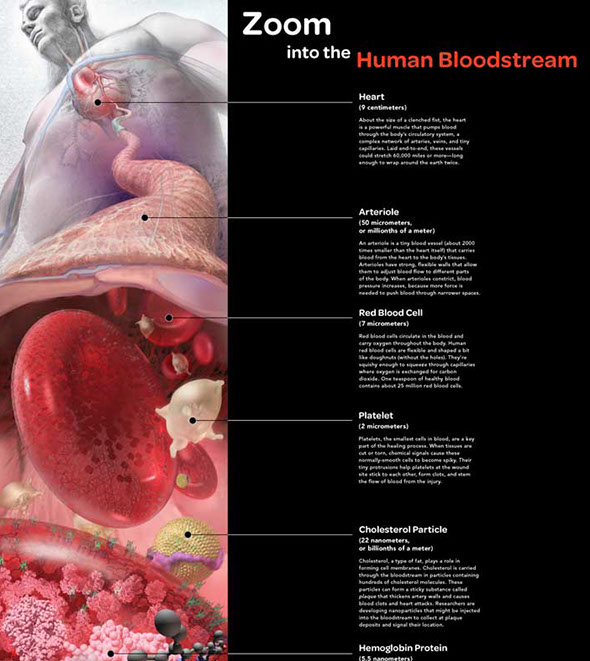

American Association for the Study of Liver Diseases syllabus cover

As part of the Exploratorium Nanoscale Science Project series, showing the human body from the heart, to arteries, to blood cells, to the hemoglobin inside, zooming forward to the molecules carrying oxygen through out the body. Awarded First Place in the Illustration category of the 2008 National Science Foundation (NSF) and Science’s International Science and Engineering Visualization Challenge.